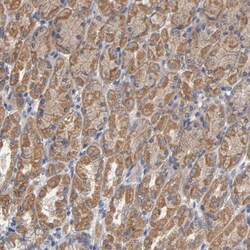

Invitrogen™ CCDC134 Polyclonal Antibody

The coiled-coil domain is a common protein motif that is often involved in protein oligomerization and is found in proteins such as transcription factors and intermediate filaments. One such protein is CCDC134, a recently identified secretory protein that has been found to inhibit the transcriptional activity of the Elk1 protein. Overexpression CCDC134 also inhibited the phosphorylation of Erk and JNK/SAPK but not p38 MAPK, while specific siRNA against CCDC134 activated Elk1 transcriptional activity and the phosphorylation of Erk and JNK/SAPK, suggesting a potential inhibiting role of CCDC134 in MAPK-mediated Elk1 transcription. CCDC134 is widely expressing in normal adult tissues, tumors, and cell lines.

| Applications | Immunohistochemistry (Paraffin), Western Blot |